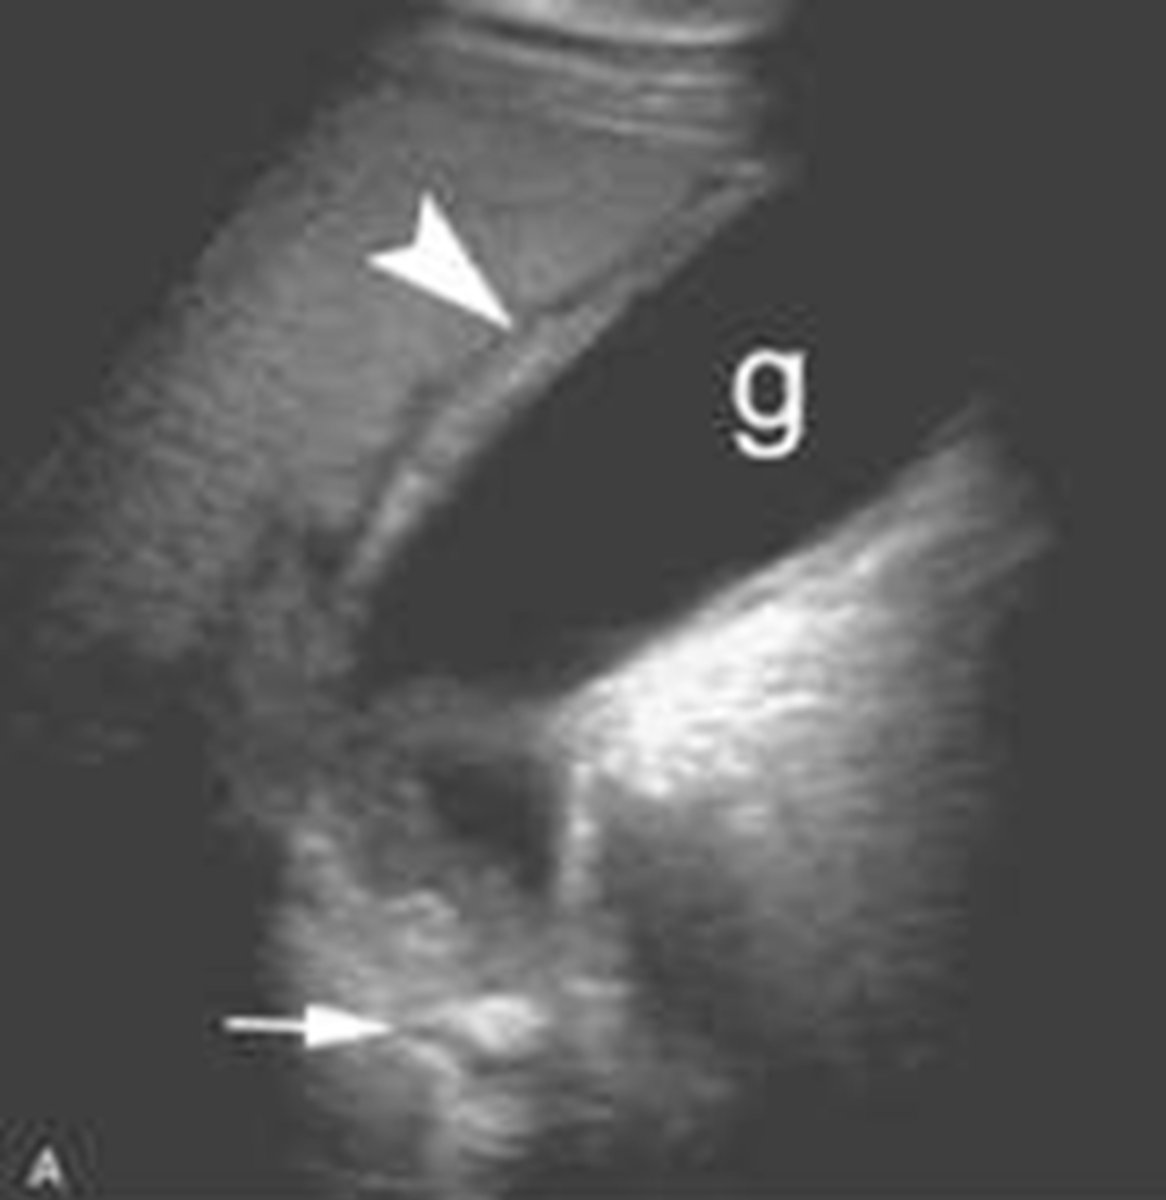

study of choice for abnormalities of biliary system

gallbladder US

gallstones

findings of acute cholecystitis

presence of gallstone (neck), thickening of gallbladder wall, fluid around gallbladder, positive murphy's sign

acute cholecystitis